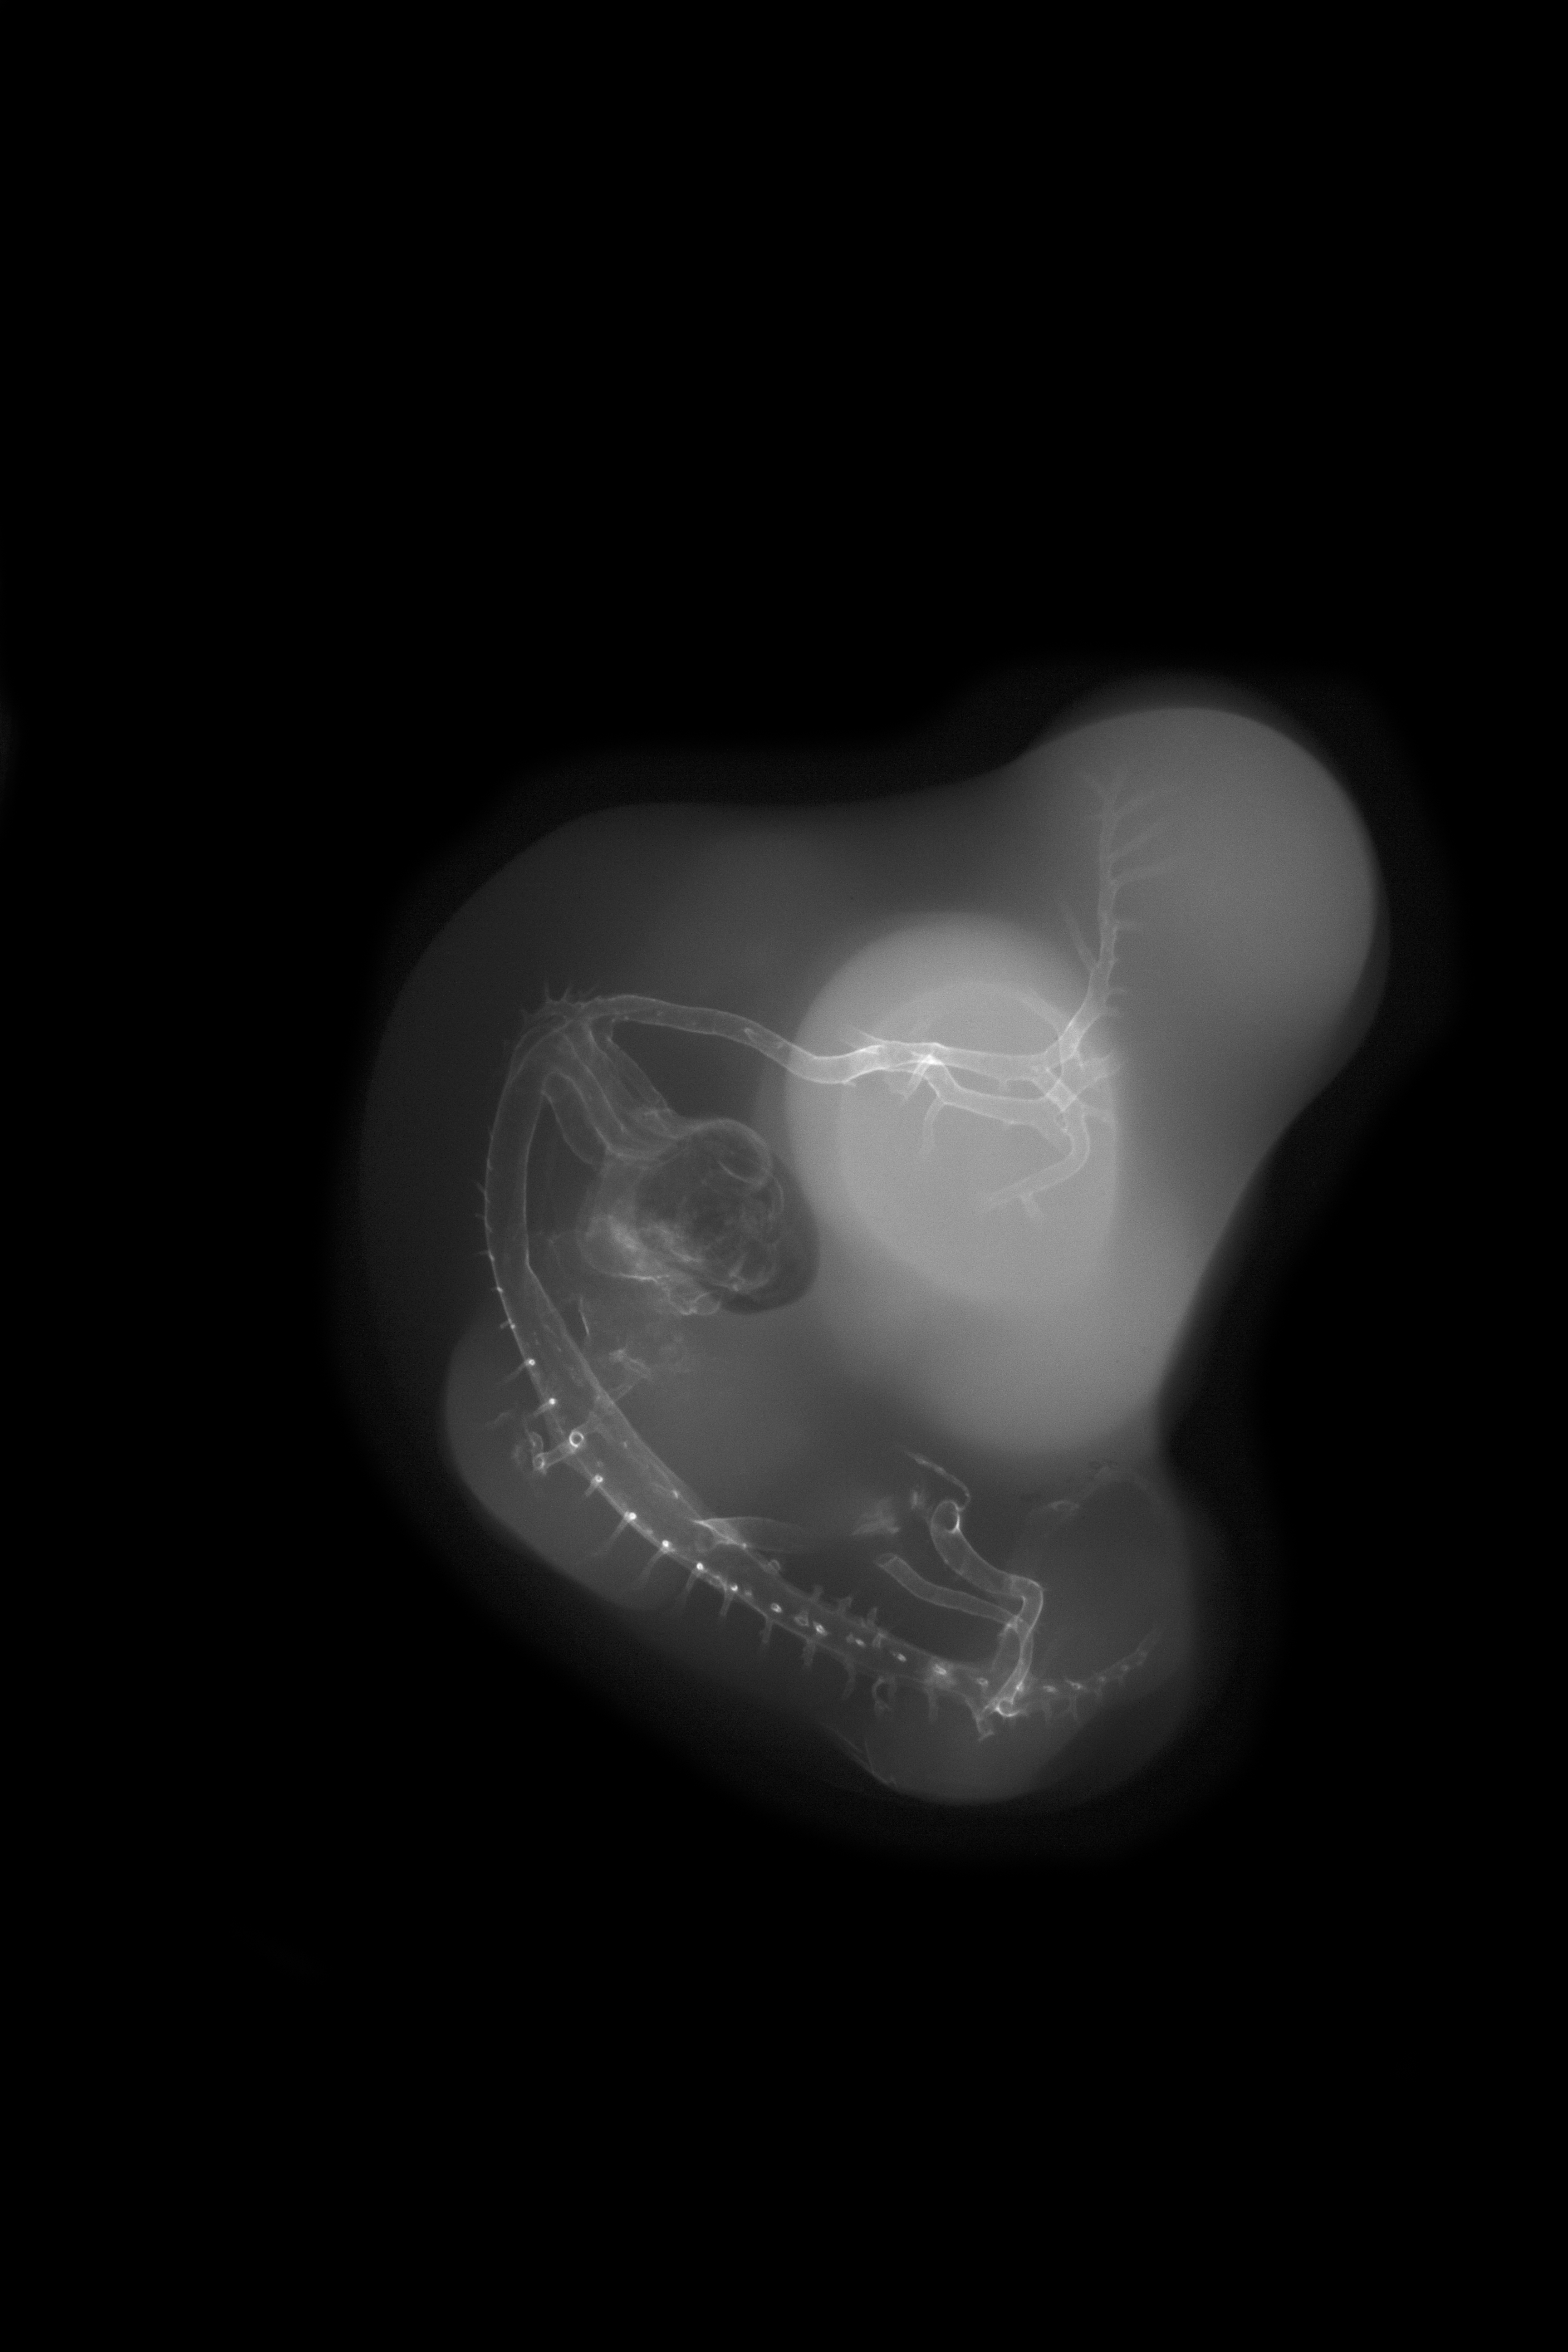

Chick Embryo Microangiography

Hamburger-Hamilton (HH) Stage 27 (approx. 5 - 5.5 days)

X-Ray Micrographs